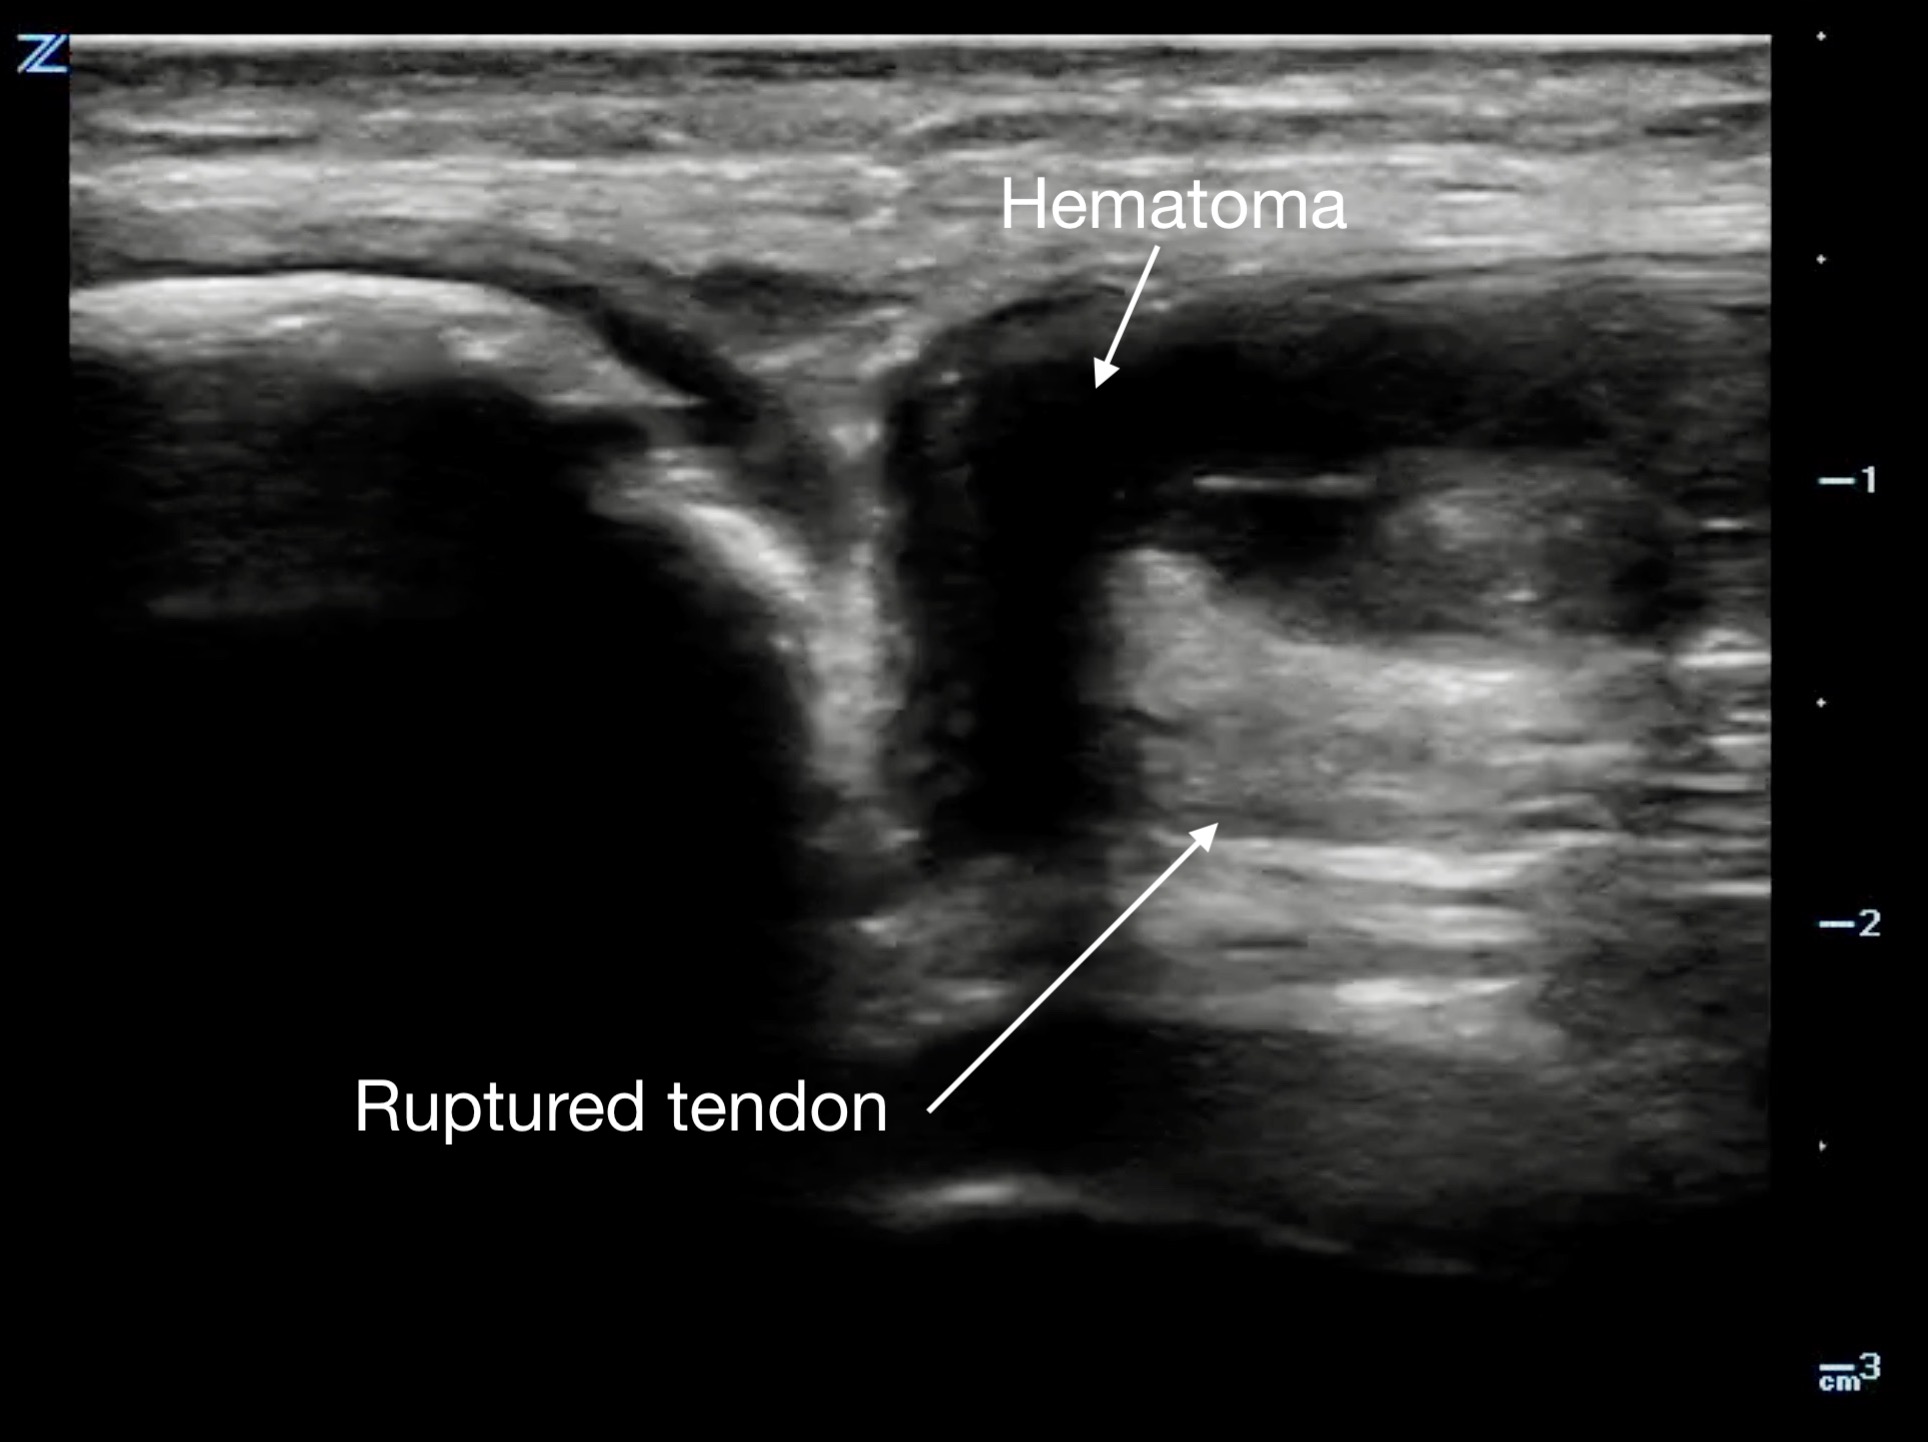

Figure 12.

Gastrocnemius muscle tear in short axis at its proximal end.

Muscle tears in biceps femoris, rectus femoris, and gastrocnemius will show a discontinuity in the muscle belly and adjacent hematoma. The associated “clapper in bell” sign is the retracted upper portion of torn muscle fibers (clapper) surrounded by hematoma (bell).19